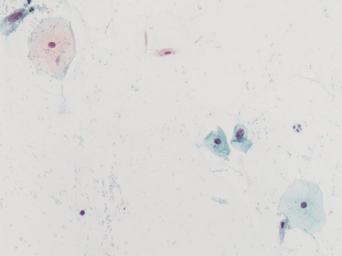

| Keywords: lesión intraepitelial escamosa de bajo grado lesiónintraepitelialescamosadebajogrado citología de cuello uterino citologíadecuellouterino citología exfoliativa ginecológica citologíaexfoliativaginecológica citología de cribado citologíadecribado citología anatomía patológica anatomíapatológica bethesda 2001 bethesda2001 osuna cérvix uterino cérvixuterino hpv españa screening lsil enfermedades de transmisión sexual enfermedadesdetransmisiónsexual imágenes de citología ginecológica imágenesdecitologíaginecológica papanicolaou test de papanicolaou testdepapanicolaou tinción de papanicolaou tincióndepapanicolaou Células con núcleo y citoplasma aumentado de tamaño, núcleos irregulares, como plumosos, tendencia al color naranja de muchas células, halos en algunos casos, núcleos dobles en otros, algunos núcleos hipercromáticos. Células con núcleo y citoplasma aumentado de tamaño, núcleos irregulares, como plumosos, tendencia al color naranja de muchas células, halos en algunos casos, núcleos dobles en otros, algunos núcleos hipercromáticos. |